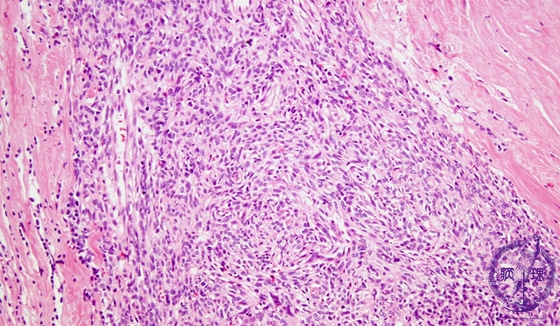

Microscopic view (low power view): WHO (World Health Organization) type A thymoma. WHO type A thymoma is an epithelial neoplasm despite having a mesenchymal appearance demonstrated by spindle cells arranged in a storiform pattern. This subtype has few or no lymphocytes.